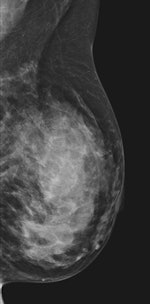

| 45-year-old asyptomatic woman with family history of breast cancer underwent mammography and MRI for screening. Full field digital mammogram is normal. Coned down view was done after MRI. MRI depicts a well circumscribed tumor with fast and early enhancement, strong wash out, and peripheral (rim) enhancement. This is high grade invasive cancer (basal-like) without calcifications; even coned down view is unremarkable. All images courtesy of Dr. Christiane Kuhl |